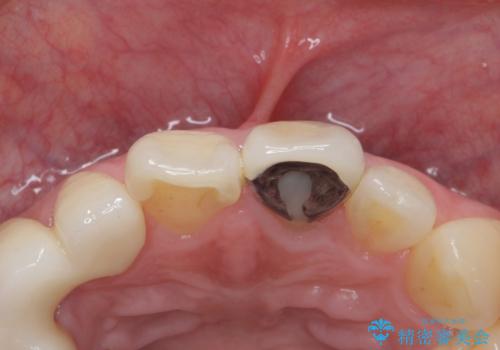

- 前歯の被せ物のやり替えを希望して来院されました。

再根管治療の後、審美性の良いジルコニアクラウンをセットしていきます。